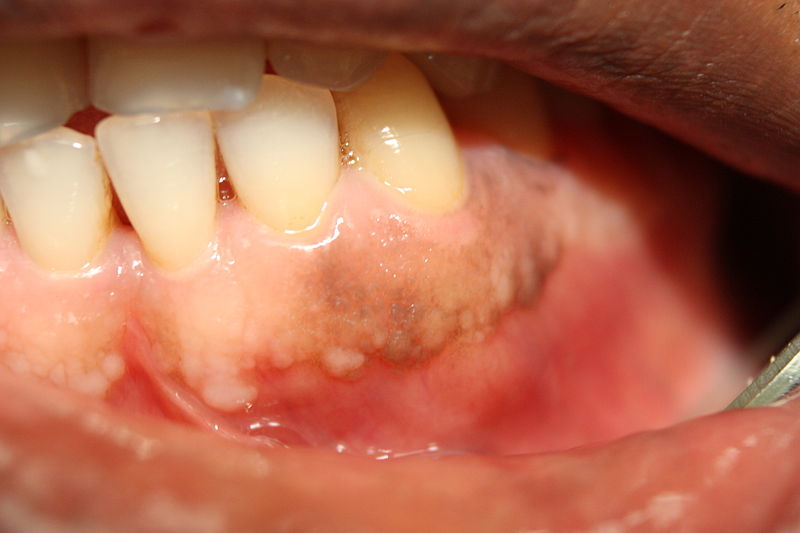

간혹 양치하다가 잇몸에서 피가 나는 경험을 합니다. 잇몸 염증의 초기 증상으로 피가 나며 잇몸이 발갛게 붓습니다. 잇몸 염증이 심해지면 피가 더 심하게 나며 아프고 입 냄새는 납니다.

잇몸의 염증을 치아주위 염증, 치주염이라고 합니다. 치주염은 최근 국민건강보험공단에 의하면 전 국민에서 가장 흔한 병으로 감기보다 더 흔한 병이 되었습니다. 치주염의 원인으로 첫 번째로는 입안에 음식 찌꺼기 때문입니다. 음식 찌꺼기에 병균이 자라면 독소를 분비하여 잇몸에 염증이 생깁니다. 두 번째 이유는 신체 면역의 저하입니다. 잇몸은 신체의 건강 상태를 나타내는 척도입니다. 건강할 때는 잇몸이 괜찮다가 피로나 스트레스로 면역력이 떨어지면 곧바로 잇몸이 들뜨고 피가 납니다. 구강에는 항상 수백만 마리의 세균들이 존재하는데 자가 면역력이 떨어지면 정상 세균보다 나쁜 세균들이 많이 증가하여 염증이 나타납니다.